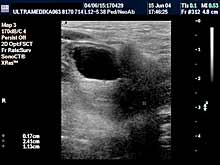

- Testisi

Pregled testisa, bez obzira da li postoji bol ili sumnja na

zapaljenje su apsolutna indikacija za pregled. Ultrazvučna

dijagnostika testisa može otkriti i zloćudni tumor testisa kod

mladih ljudi kod kojih su testisi normalnih karakteristika nakon

kliničkog pregleda pipanjem od strane lekara. Ultrazvučna rana

dijagnostika je osnovni preduslov za uspešno lečenje. Otkrivanje

proširenih vena testisa i nakon toga hirurška intervencija

sprečavaju pojavu smanjene proizvodnje spermatozoida.